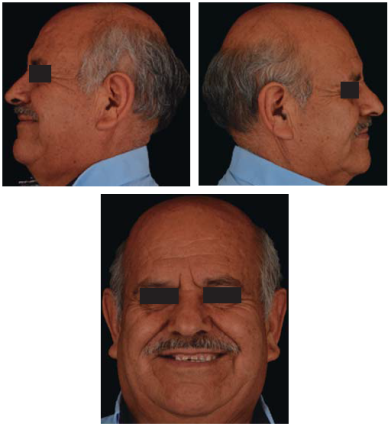

Este reporte documenta el tratamiento de un paciente masculino de 68 años de edad. Comenta tener dificultades masticatorias y digestivas debido a importante desgaste dental, se dice incómodo al sonreír; no refirió padecimientos sistémicos, fumó durante ocho años, diagnosticado con hipertensión arterial controlada. Se observa atrición generalizada, ausencia de dientes 14, 15, 16, 46 y periodonto sano (Figuras 1a4). Los dientes 13 y 37 presentaban tratamiento de conductos y periápice sano, sin restauración (Figura 5).

Para cuantificar la reducción de DVO, se examinó el perfil facial y la estética mediante análisis fotográfico y vídeo (Figuras 6y7). Además de realizar un cuidadoso análisis del montaje de los modelos diagnósticos en articulador semiajustable (Figura 8). También se examinó el esquema oclusal (presentaba relación borde a borde) y la estructura dental con la que se contaba (Figura 3). La revisión dinámica fue clave para determinar que el paciente exhibe una línea de sonrisa alta (Figura 9).

Se controló al paciente por espacio de un mes y medio para verificar su fase de adaptabilidad al tratamiento y su condición fue satisfactoriamente estable, cómoda y sobre todo funcional (Figuras 42a45).